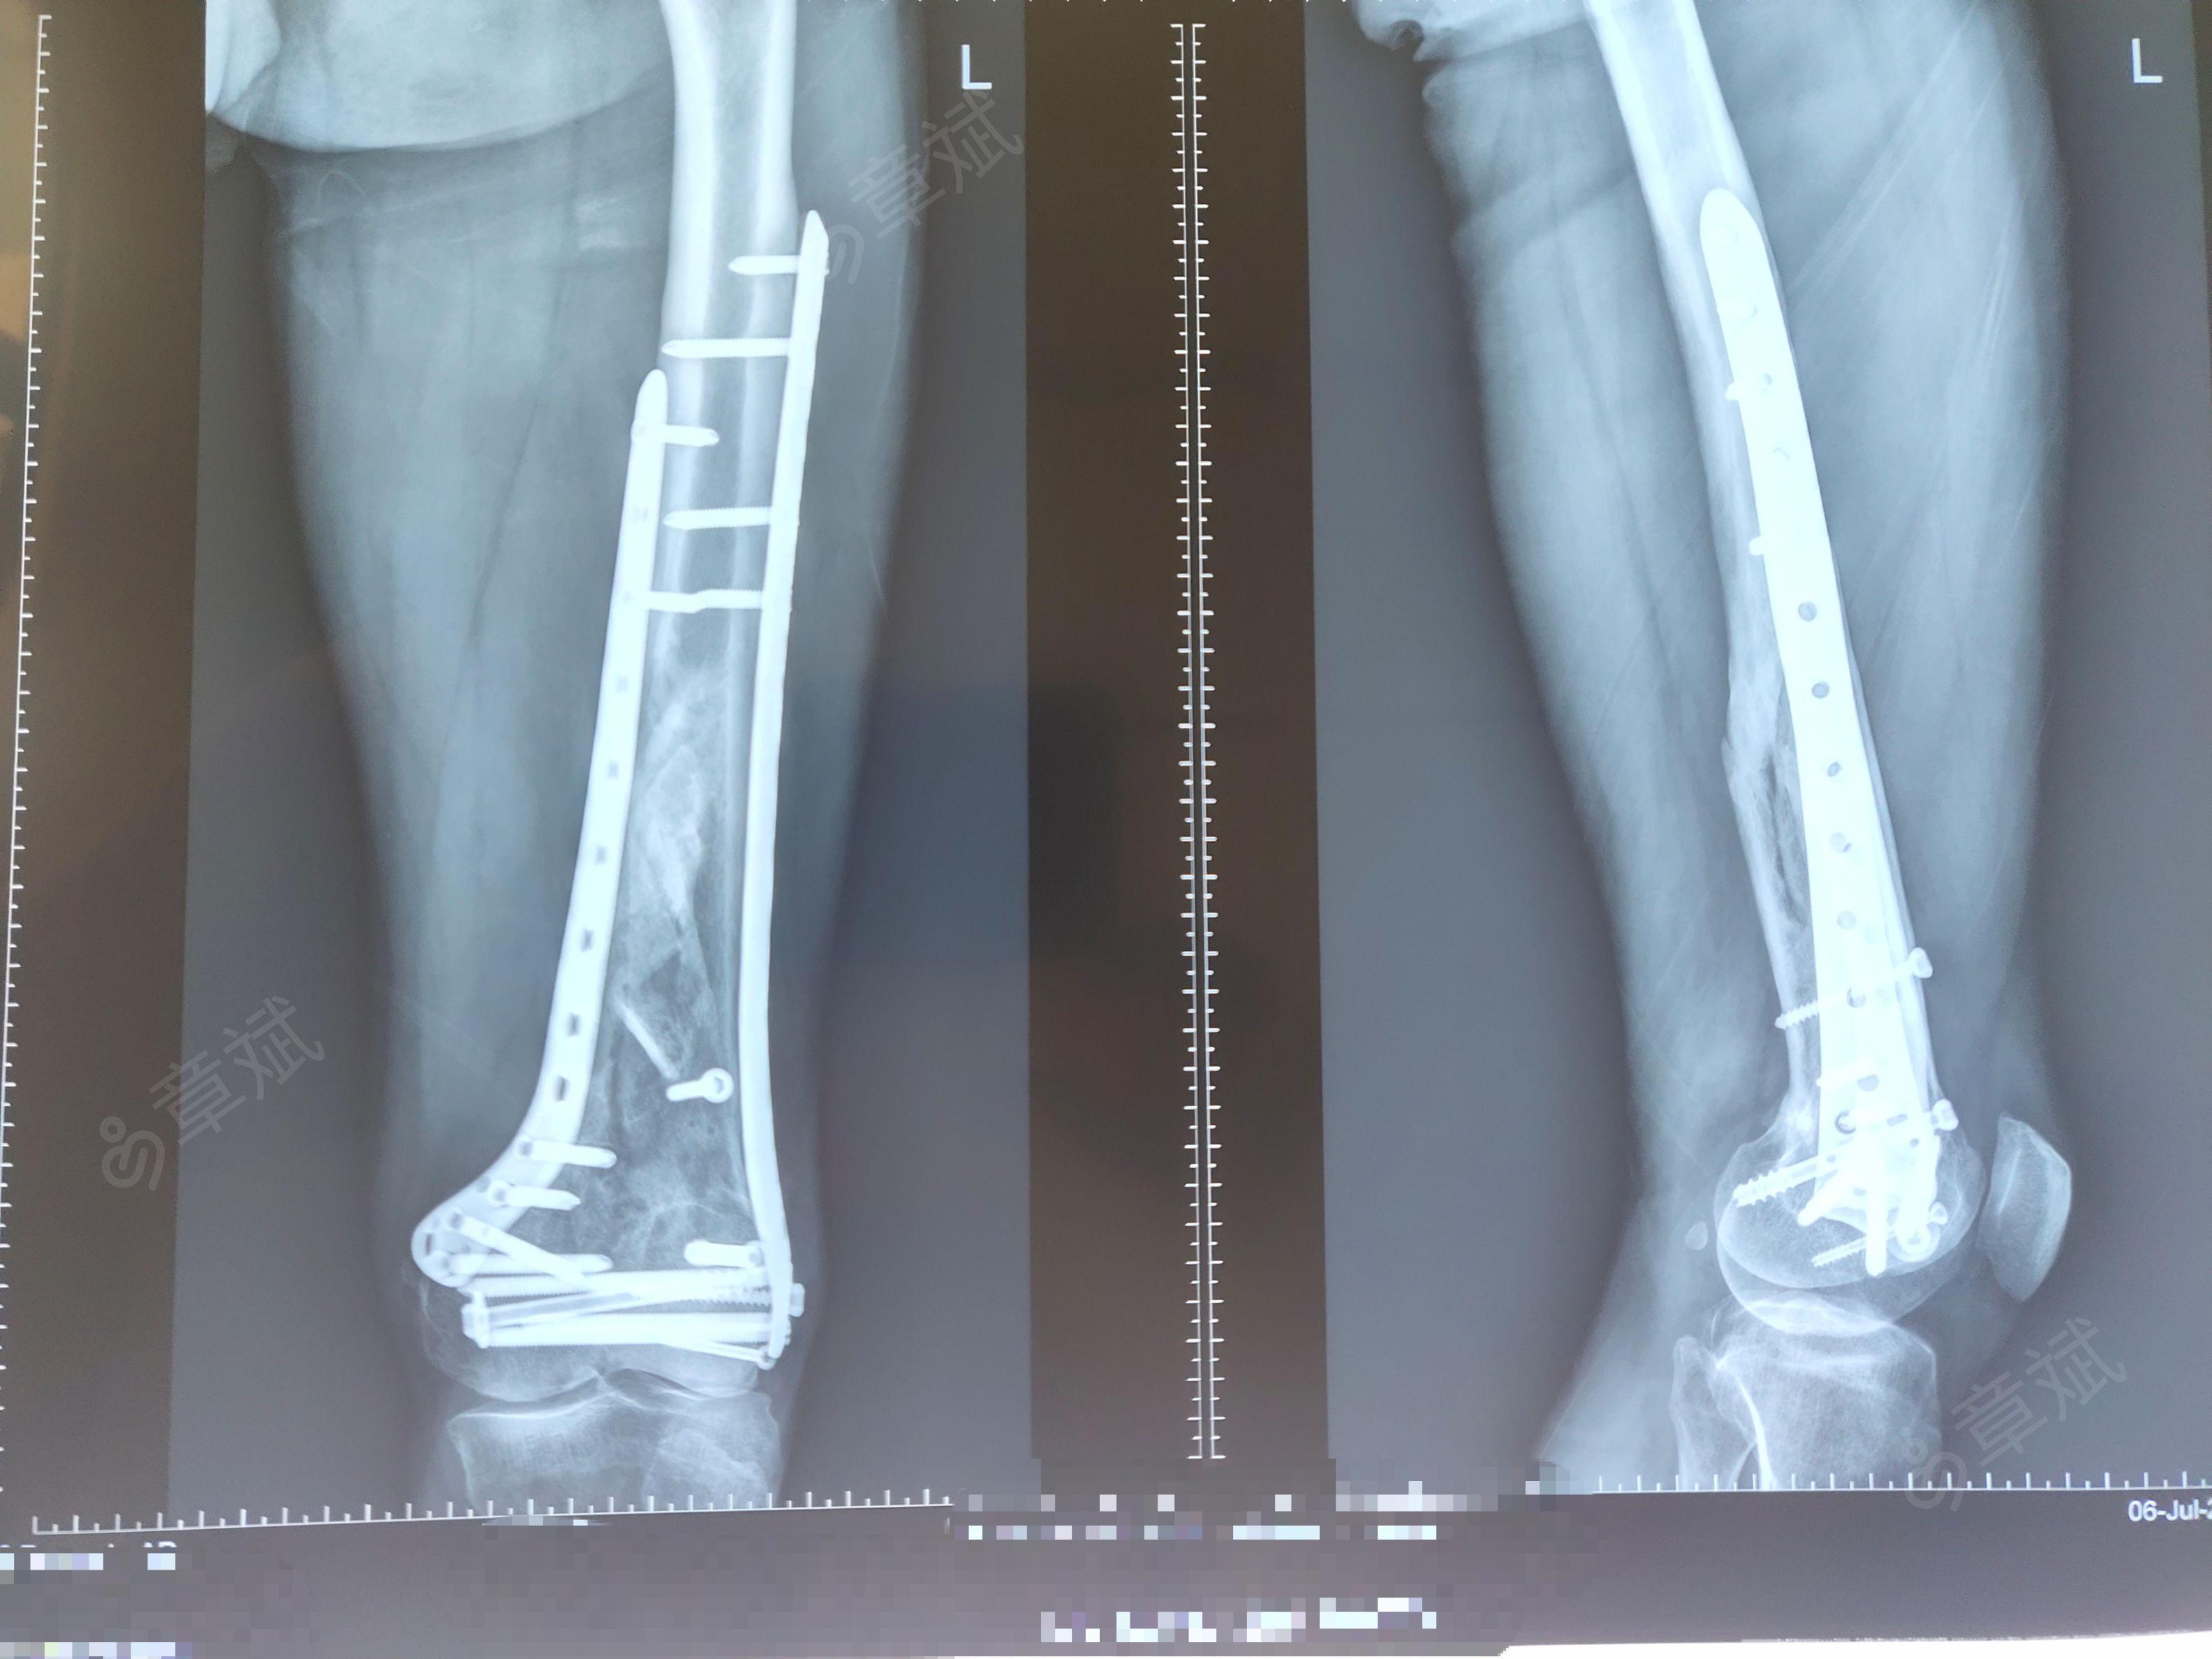

左股骨髁间髁上粉碎性骨折 [病例帖]

左股骨髁上骨折